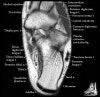

발목 관절의 MRI 단면 영상

- Sagittal section

Bones and marrow

Joint fluid

Talar dome

Subtalar joints

Achille's tendon

Sinus tarsi

Plantar fascia